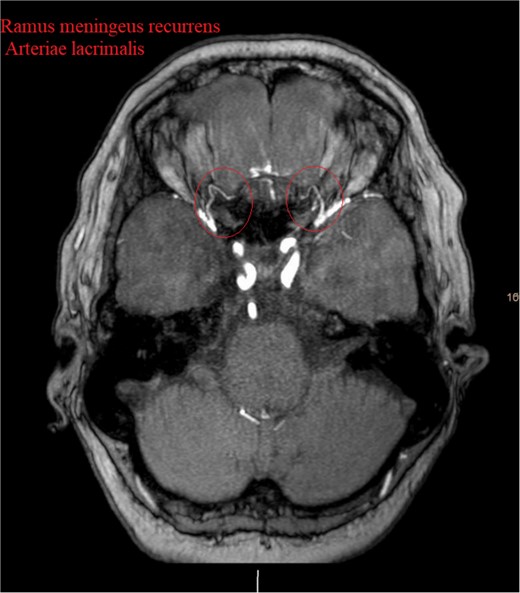

Show the MRA with the bilateral anastomotic branch of the lacrimal artery with the middle meningeal artery.

In our case, a notable feature was the circular anastomosis among arterial branches, reminiscent of the unique Hyrtl anastomosis [5]. This configuration resembled the meningeolacrimal variant of the Ramus lacrimalis originating from the middle meningeal artery, traversing the Hyrtl canal (HC) [1]. The HC, positioned variably lateral to the superior orbital fissure, is linked to the persistence of an embryonic canal for the supraorbital division of the stapedial artery, forming a canal for bilateral anastomosis between the orbital branch of the middle meningeal artery and the lacrimal branch of the ophthalmic artery in 26% of cases [1]. This finding offers a unique perspective on the vascular considerations associated with our case’s meningioma blood supply.